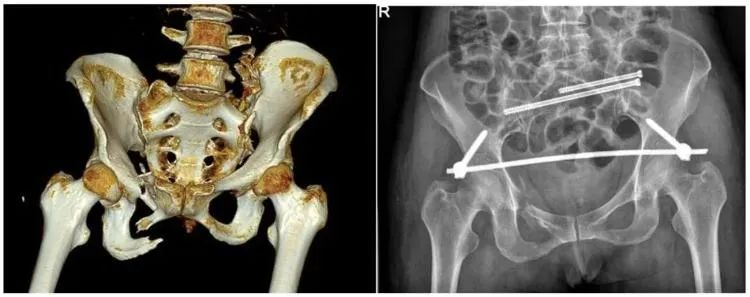

二、穩定性骨折&不穩定性骨折

另外,我們根據骨盆骨折是否穩定可以分為穩定性的骨折和不穩定性的骨折。如果是不穩定性的骨折醫生可能會建議病人進行手術治療,把不穩定性的骨折變成穩定性的骨折。

【醫療科普】:不穩定性骨折影像

不穩定性骨折

普愛醫療推出的大平板一體式C形臂PLX119C,配置30cm×30cm平板探測器,大視野,能夠呈現更多圖像細節,對于諸如骨盆雙側骨折類型手術或骨盆后環內固定術具有應用優勢,一次曝光可獲取全部骨折部位影像,可簡化曝光流程,提高手術效率。